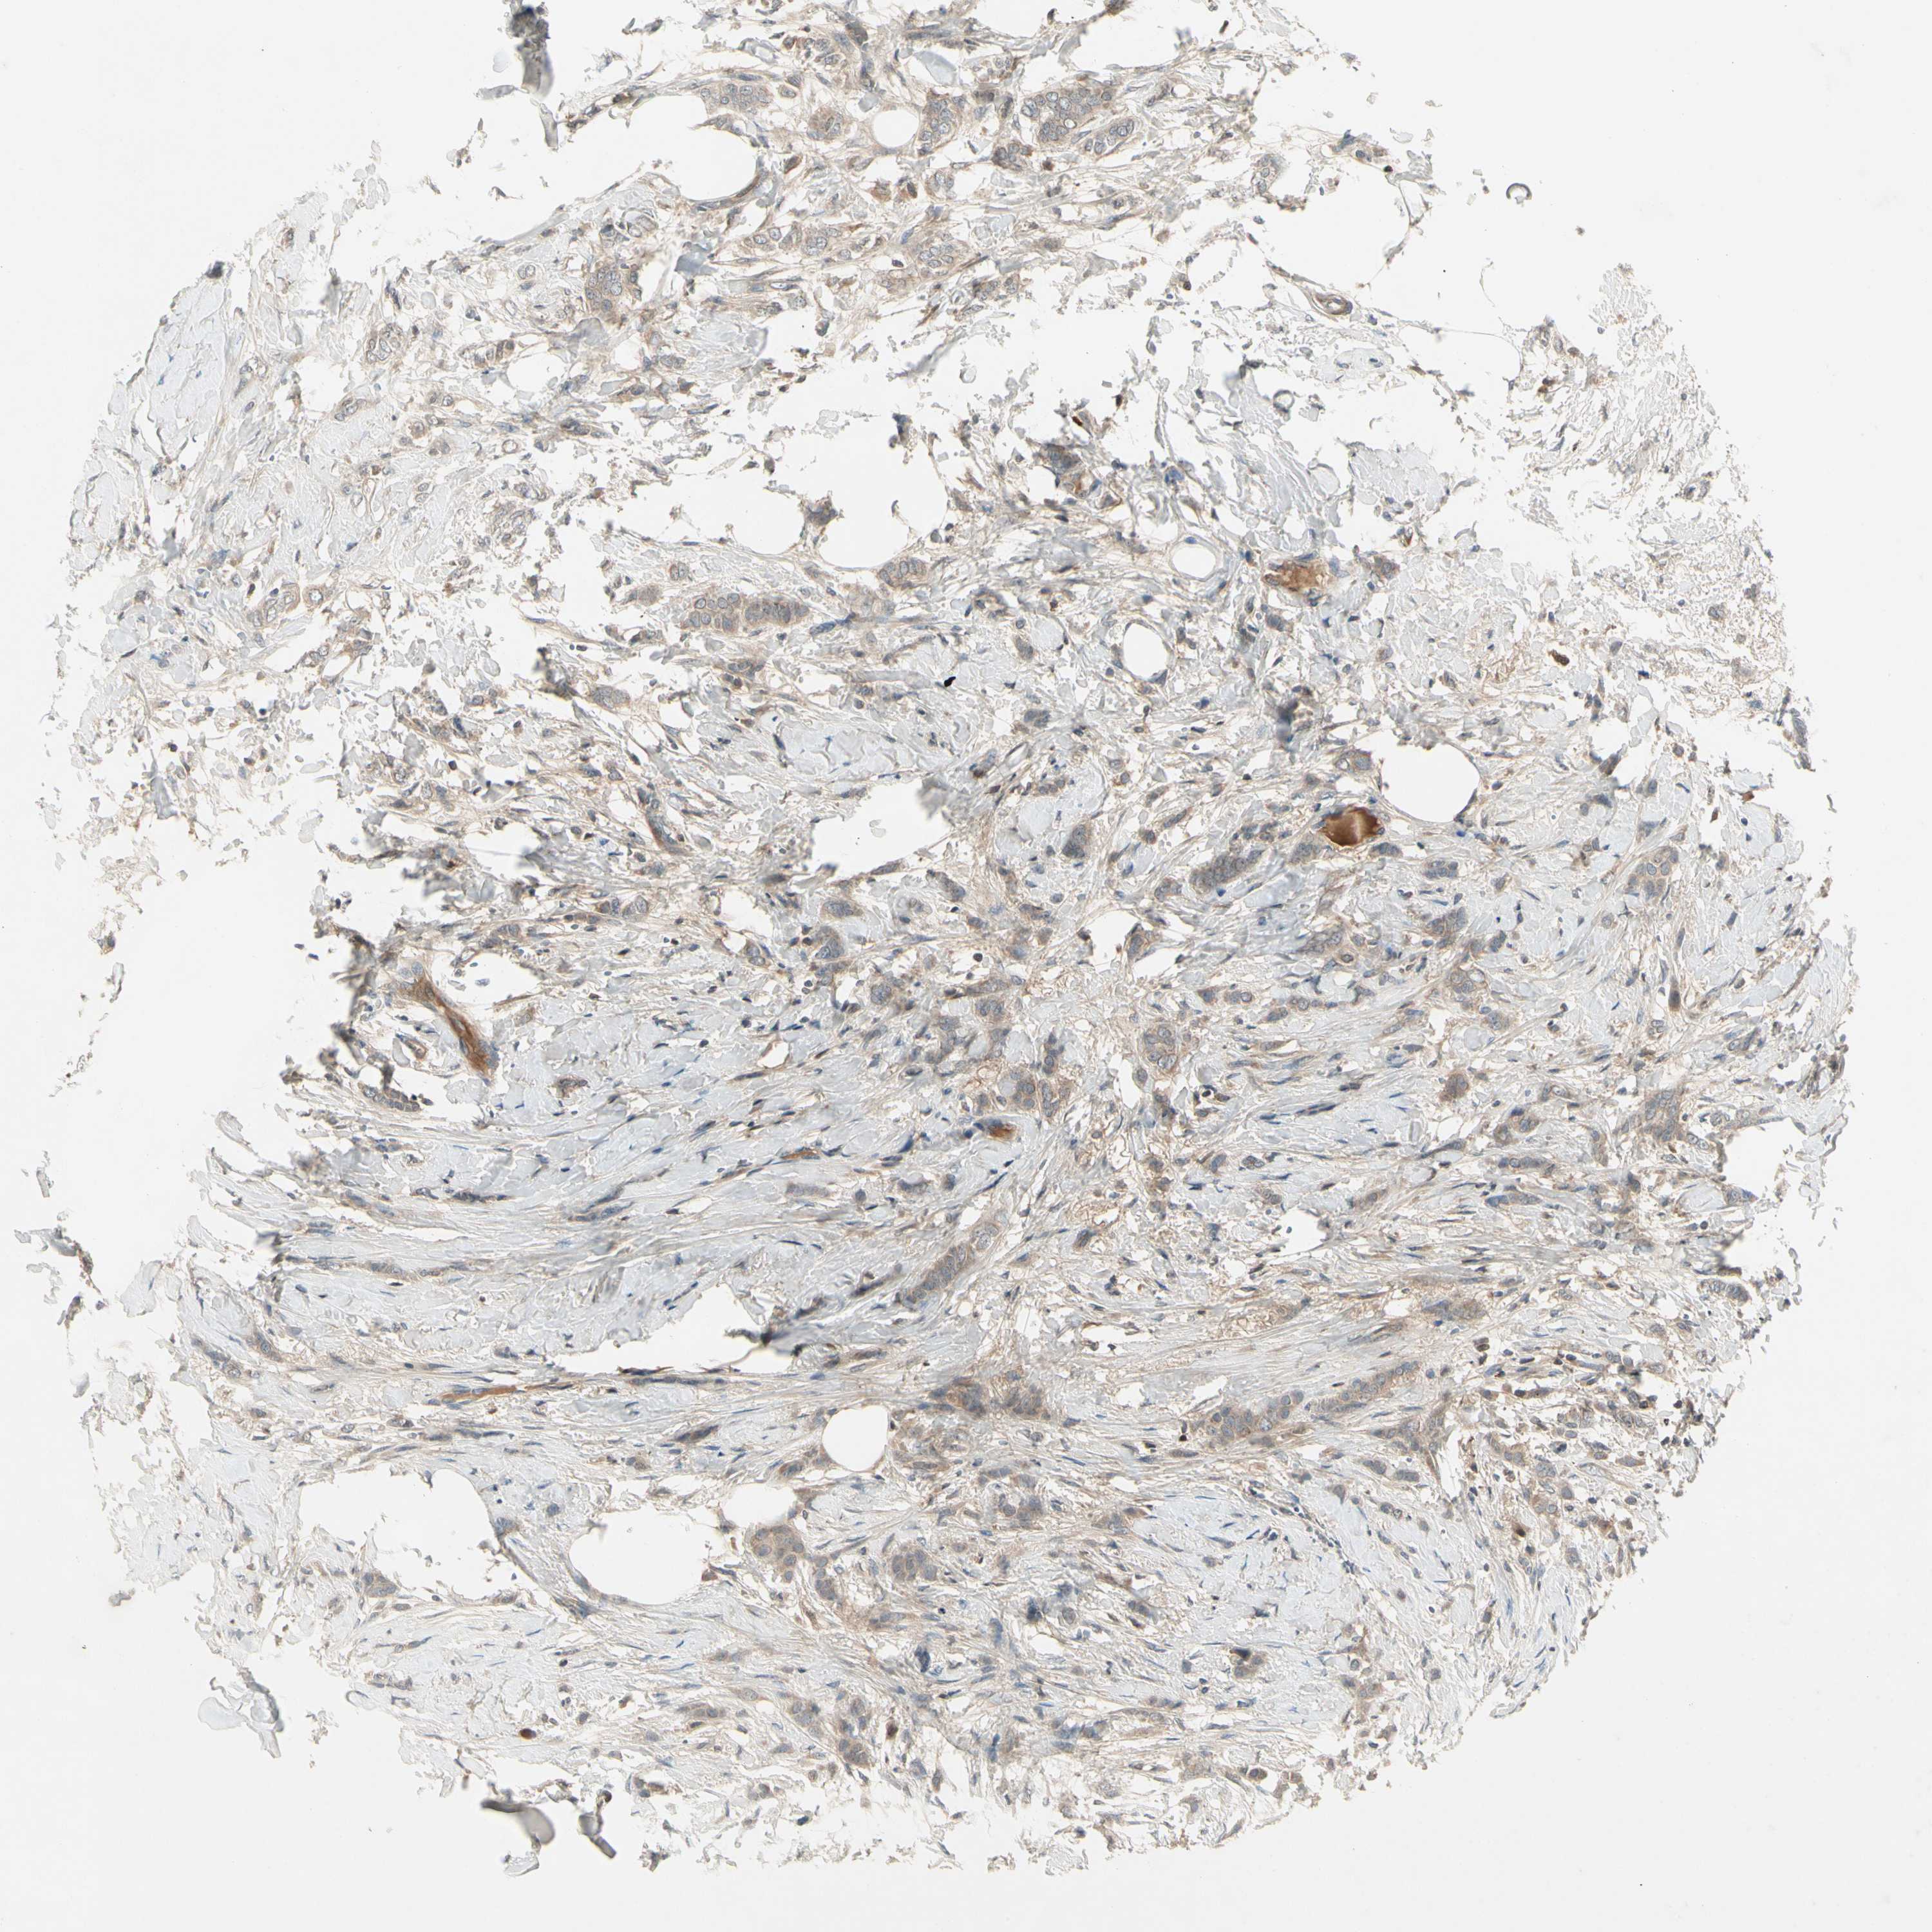

CANCER BREAST CANCER Show tissue menu

BRCA TCGA BRCA VALIDATION PROTEIN EXPRESSION

Breast cancer

Human cancer